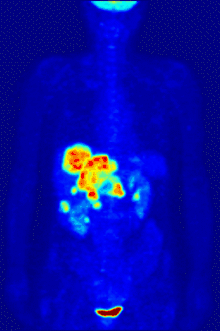

يعتبر التصوير المقطعي بالإصدار البوزيتروني (يرمز لها اختصاراً PET من Positron Emission Tomography) هي تقنية تصوير في الطب النووي تبين صور ثلاثية الأبعاد لبعض أعضاء الجسم وما قد يكون فيها من ورم سرطاني أو نقيلات سرطانية ، كما يمكن بواسطتها تفقد مختلف العمليات الوظيفية في الجسم، مثل العمليات الحيوية للجهاز الهضمي. ويعمل الجهاز المصوّر على أساس اكتشاف أزواج من أشعة غاما المنبثفة بشكل غير مباشر من نظير مشع يكون مصدرا للبوزيترونات (إلكترونات موجبة الشحنة) . يتم حقن المادة المشعة في جسم المريض بعد ربطه بجزيء حيوي فعال (مثل جزيء سكر) ، فتتركز المادة المشعة بالعضو المراد فحصه، مثل الدماغ أو الكلى أو الكبد . ثم يتم تسجيل القياسات لأشعة غاما الصادرة من العضو واستبناء صورة ثلاثية الأبعاد لها بواسطة الحاسوب، فيمكن رؤياها على شاشة متصلة بالحاسوب. في الآونة الأخيرة، أصبحت تستعمل طريقتين في نفس الوقت لزيادة التوضيح والاستبناء، وهي طريقتي التصوير الطبقي المحوسب بواسطة الأشعة السينية (أشعة إكس) وتكون مقترنة بالتصوير المقطعي بالإصدار البوزيتروني .

إذا كان الجزيء الفعال حيويًا الذي يرتبط بالقائفة هو جزيء الـFDG (إحدى مضاهئات الجلوكوز)، فإنّ تصوير تركيز القائفة يعطي قياسًا لحجم وشكل الورم في العضو المصاب أو يوضح سير فعالية في التمثيل الغذائي. مع أنّ استعمال هذه القائفة بات شائعًا في التصوير المقطعي بالإصدار البوزيتروني، فهنالك العديد من القائفات الأخرى التي تختص بالتمركز في أعضاء معينة في الجسم.